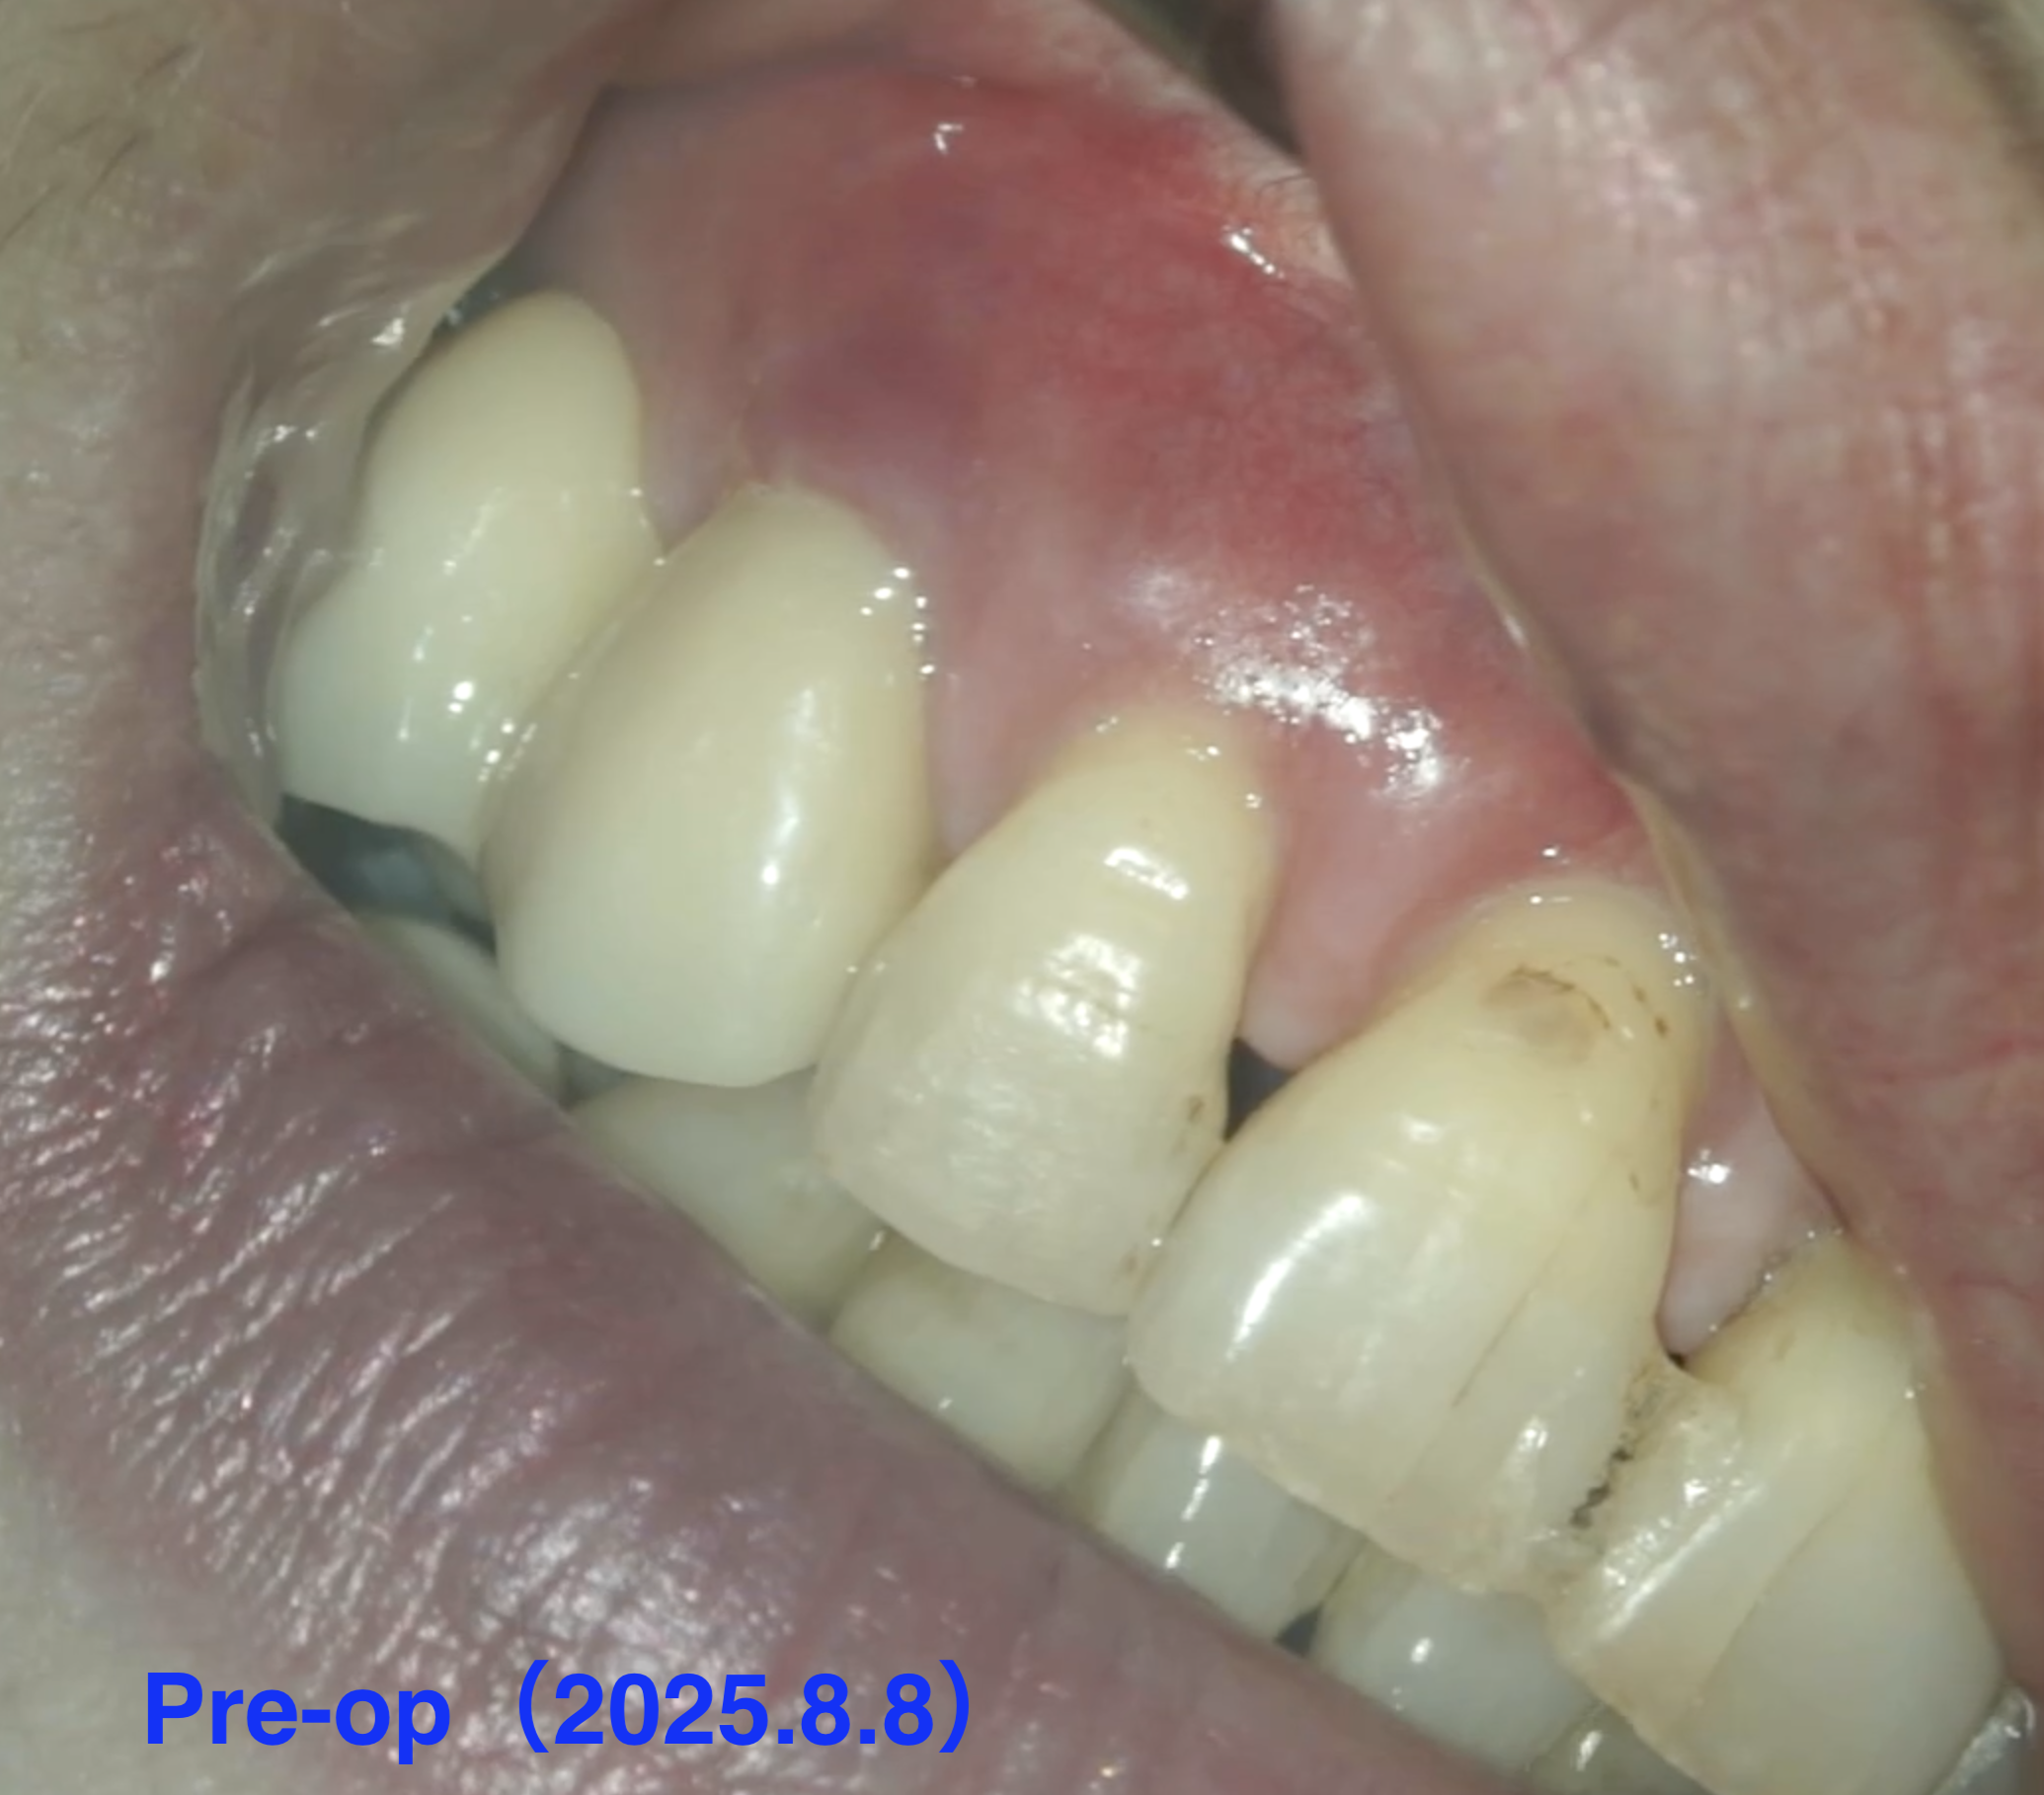

紹介患者さんの治療。

主訴は、

右上のブリッジ治療をしている時から歯茎が腫れて、歯に穴が空いていると言われたがせっかく入れたばかりのセラミックのブリッジを外したくない。

Pre-op Endo test(2025.8.8)

歯牙の表面に外部吸収がある。

学術的には歯髄には及ばないと言われているが画像的には到達済みだろう。

Pulp Dx: Chronic apical abscess

Periapical Dx: Symptomatic apical periodontitis

Recommended Tx: Invasive cervical root resorption repair, RCT/Apicoectomy